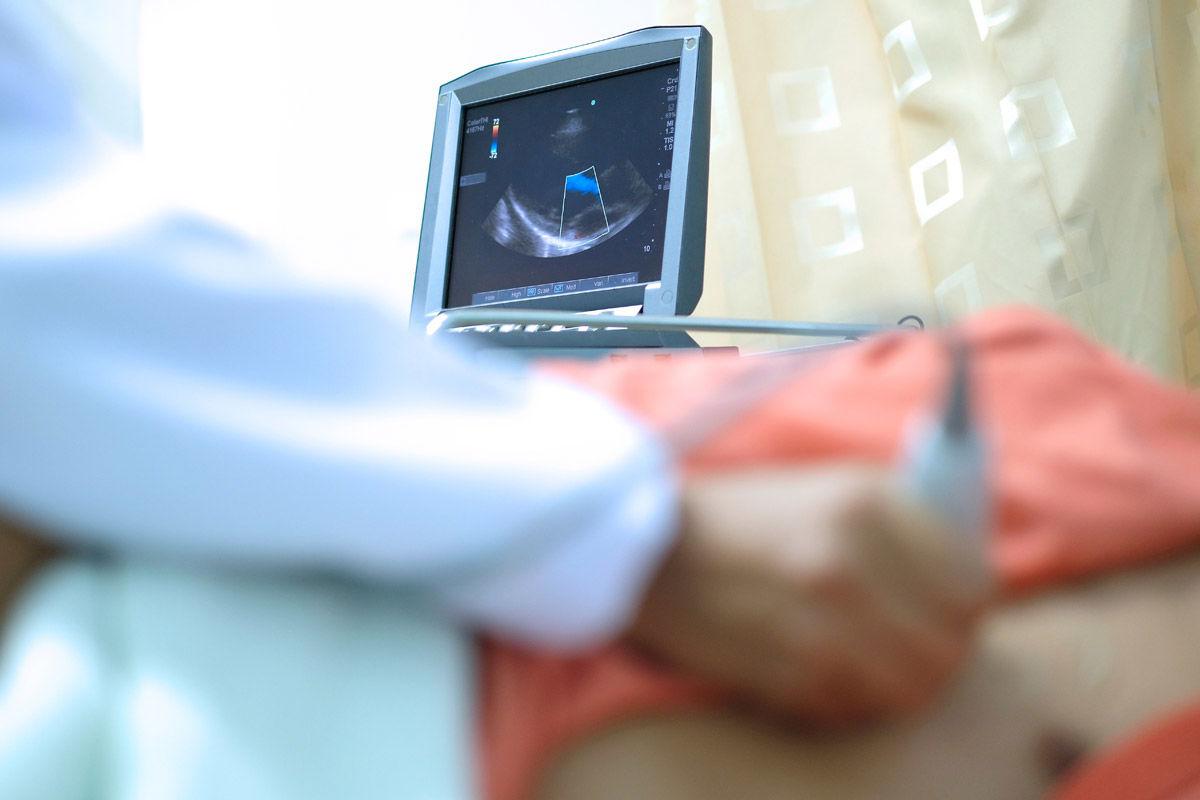

The Highly Advanced Technology our experts use to assess the functions of Blood Vessels & Cardiovascular Systems by turning sound waves into images.